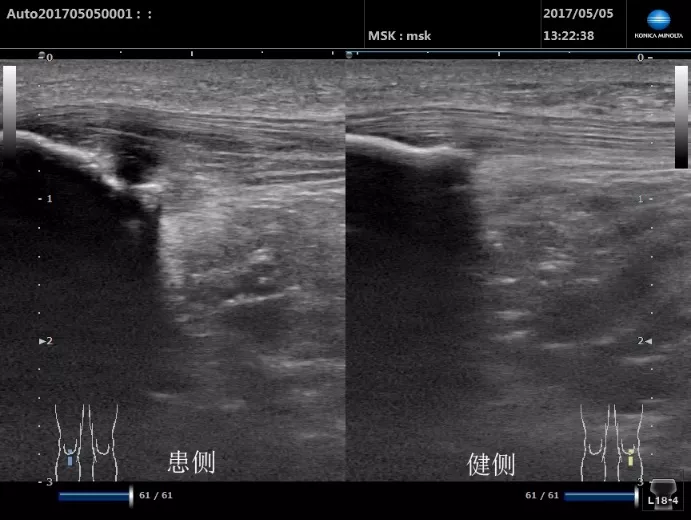

超聲掃查髕腱炎顯示為肌腱腫脹、回聲減低,其內肌腱纖維保持連續,附著處可能出現骨皮質不光滑。